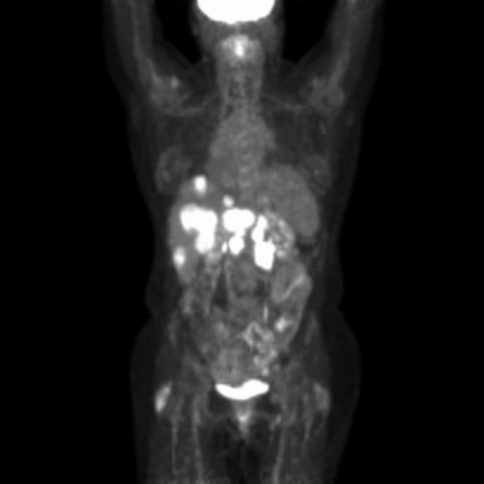

In 2017, I began treating a 52-year-old otherwise healthy female with stage IV high-grade neuroendocrine tumor of the pancreas. She presented with metastases to the liver, peripancreatic lymph nodes, and abdominal pain. I treated her with combination chemotherapy, and she had improvement of her abdominal pain but suffered the inevitable side effects of the treatment. After one year on different combinations of chemotherapy, her disease progressed with increasing pain and increasing size of the liver and peripancreatic metastases. We began treatment with dual agent immunotherapy, and after three treatments, she had a dramatic clinical benefit and reduction in the size of the metastases. See Figure 2. The patient had side effects of diarrhea and pneumonitis, which are controlled on steroids. Recently, she suffered a stroke and is currently off treatment, recovering well and remains in remission.